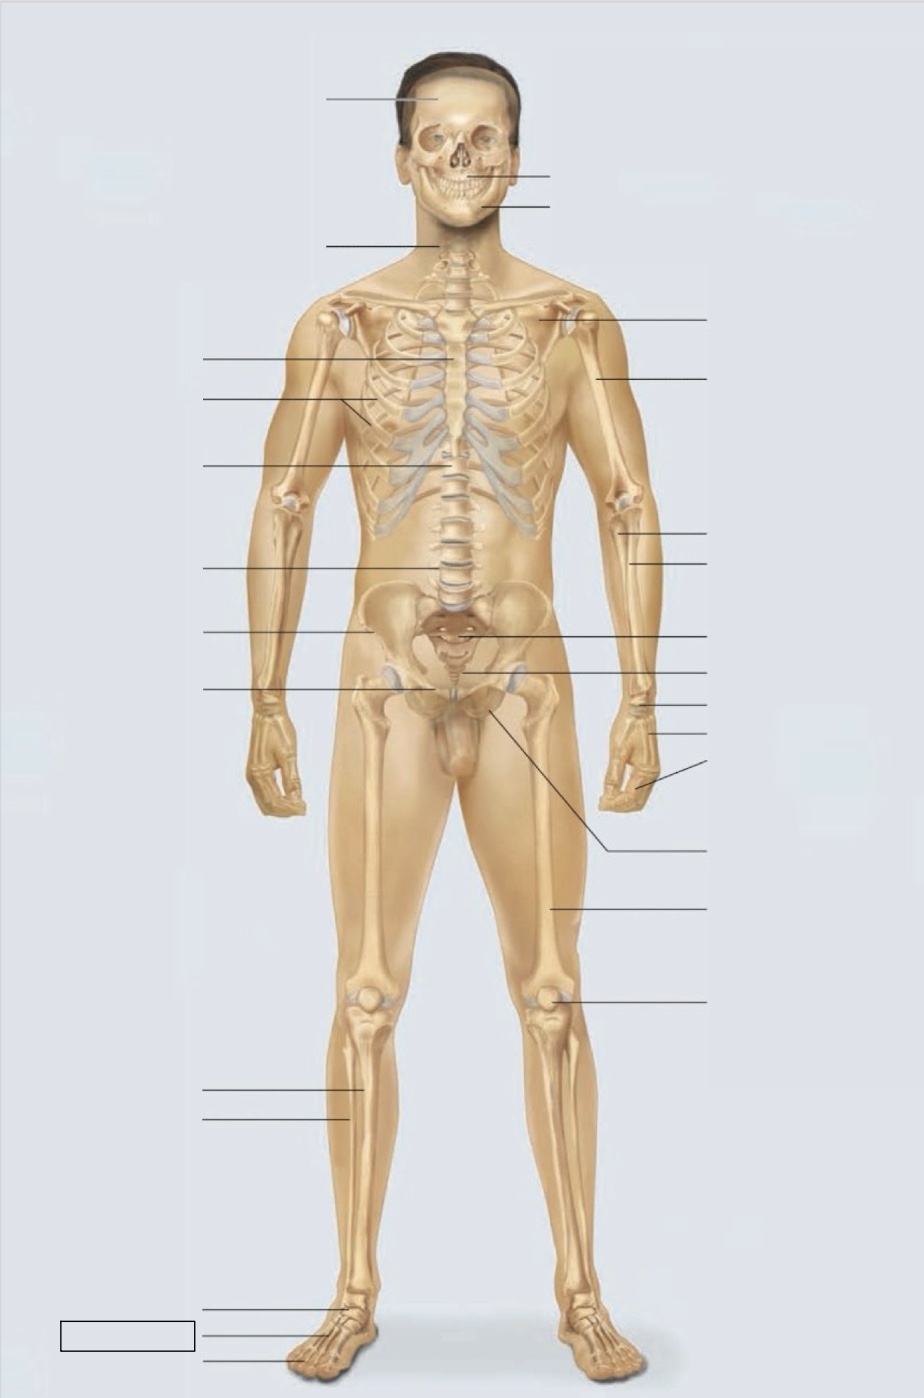

maxilla

mandible

scapula

humerus

ulna

radius

sacrum

coccyx

carpals

metacarpals

phalanges

ischium

femur

patella

phalanges

metatarsals

tarsals

fibula

tibia

pubis

ilium

lumbar vertebrae (L4)

thoracic vertebrae (T11)

ribs

sternum

cervical vertebrae

skull